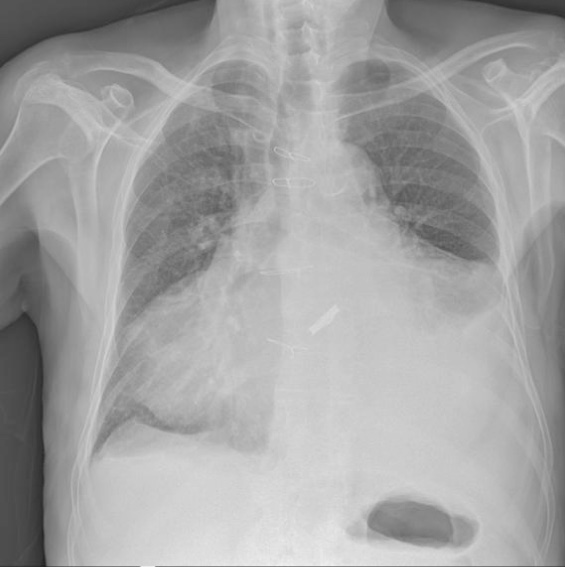

Nel 2011 venne ricoverato in Neurologia per trauma cranico contusivo da caduta a terra in casa. La TAC rilevava, tra l’altro, puntiformi chiazzette iperdense in sede frontale, scomparse in successivo controllo, per le quali si intraprendeva terapia con eparina a basso peso molecolare – EBPM – in sostituzione temporanea della TAO. Dall’elettroencefalogramma (EEG) si rilevavano tracciati irregolari per anomalie lente sulle derivazioni emisferiche di sinistra, più evidenti su quelle centro-parietali. L’Rx torace evidenziava cardiomegalia e versamento pleurico sinistro (Figura 2). Durante la degenza non venivano segnalati né dispnea né edemi declivi.

Figura 2. Rx torace (anno 2011): cardiomegalia, versamento pleurico sinistro